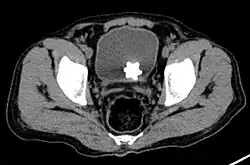

The diagnosis of bladder stone includes urinalysis, ultrasonography, x rays or cystoscopy (inserting a small thin camera into the urethra and viewing the bladder). The intravenous pyelogram can also be used to assess the presence of kidney stones. This test involves injecting a radiocontrast agent which is passed into the urinary system. X-ray images are then obtained every few minutes to determine if there is any obstruction to the contrast as it is excreted into the bladder. Today, intravenous pyelogram has been replaced at many health centers by CT scans. CT scans are more sensitive and can identify very small stones not seen by other tests.[8]

Jackstone calculus

Jackstone calculi are rare bladder stones that have an appearance resembling toy jacks. They are almost always composed of calcium oxalate dihydrate and consist of a dense central core and radiating spicules. They are typically light brown with dark patches and are usually formed in the urinary bladder and rarely in the upper urinary tract. Their appearance on plain radiographs and computed tomography in human patients is usually easily recognizable. Jackstones often must be removed via cystolithotomy.[10]